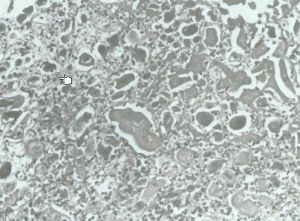

表皮細胞發生氣球樣變性、網狀變性和凝固壞死,開始細胞核內可見嗜鹼性包涵體,後期變為嗜酸性包涵體,真皮乳頭輕度水腫及炎性細胞浸潤。反應重時亦有血管炎表現。